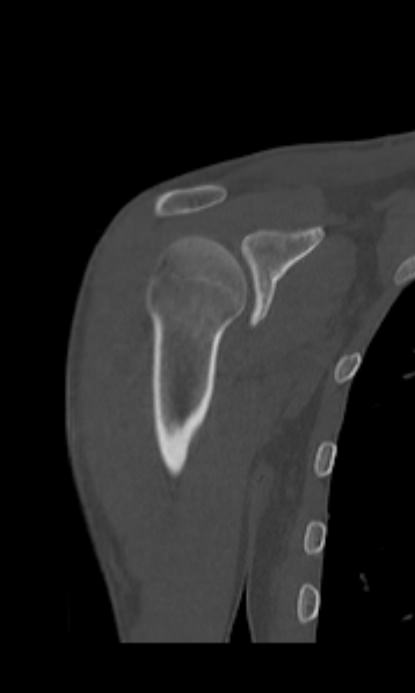

Мультиспиральная компьютерная томография является наилучшим методом диагностики патологии костной ткани и применяется для выявления различных патологических процессов в области плечевой кости.

Методика КТ построена на использовании ионизирующего излучения, которое в разной степени поглощается органами и тканями человека. Рентгеновские лучи лучше всего поглощаются костными структурами, поэтому на послойных изображениях, полученных при КТ-сканировании, хорошо видна плотность и внутреннее строение плечевой кости, а также плечевого и локтевого суставов. При этом визуализируются костные повреждения, очаги деструкции, воспалительные изменения.

Что показывает КТ плечевой кости

- повреждения костей в результате полученной травмы – трещины, переломы, смещения.